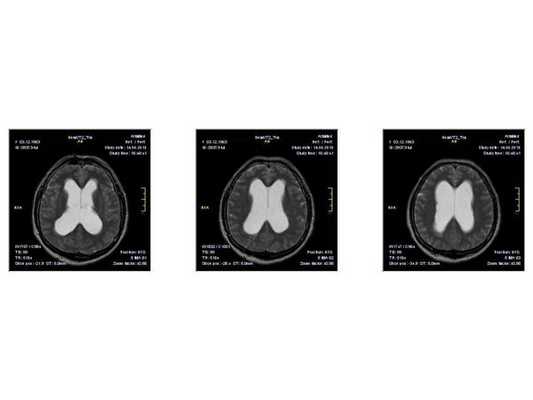

По заключению МРТ от 14.05.2013, после операции в левом полушарии мозжечка появились кистозно-глиозные изменения (на месте повреждённых нейронов образовались рубцовая ткань), а также выраженная внутренняя асимметричная гидроцефалия (избыточное скопление спинномозговой жидкости в полости черепа).

- МРТ в динамике показывает постепенное сужение желудочковой системы на 2 мм. Для сравнения представлены снимки МРТ от 14.05.2013 и от 16.10.2014.